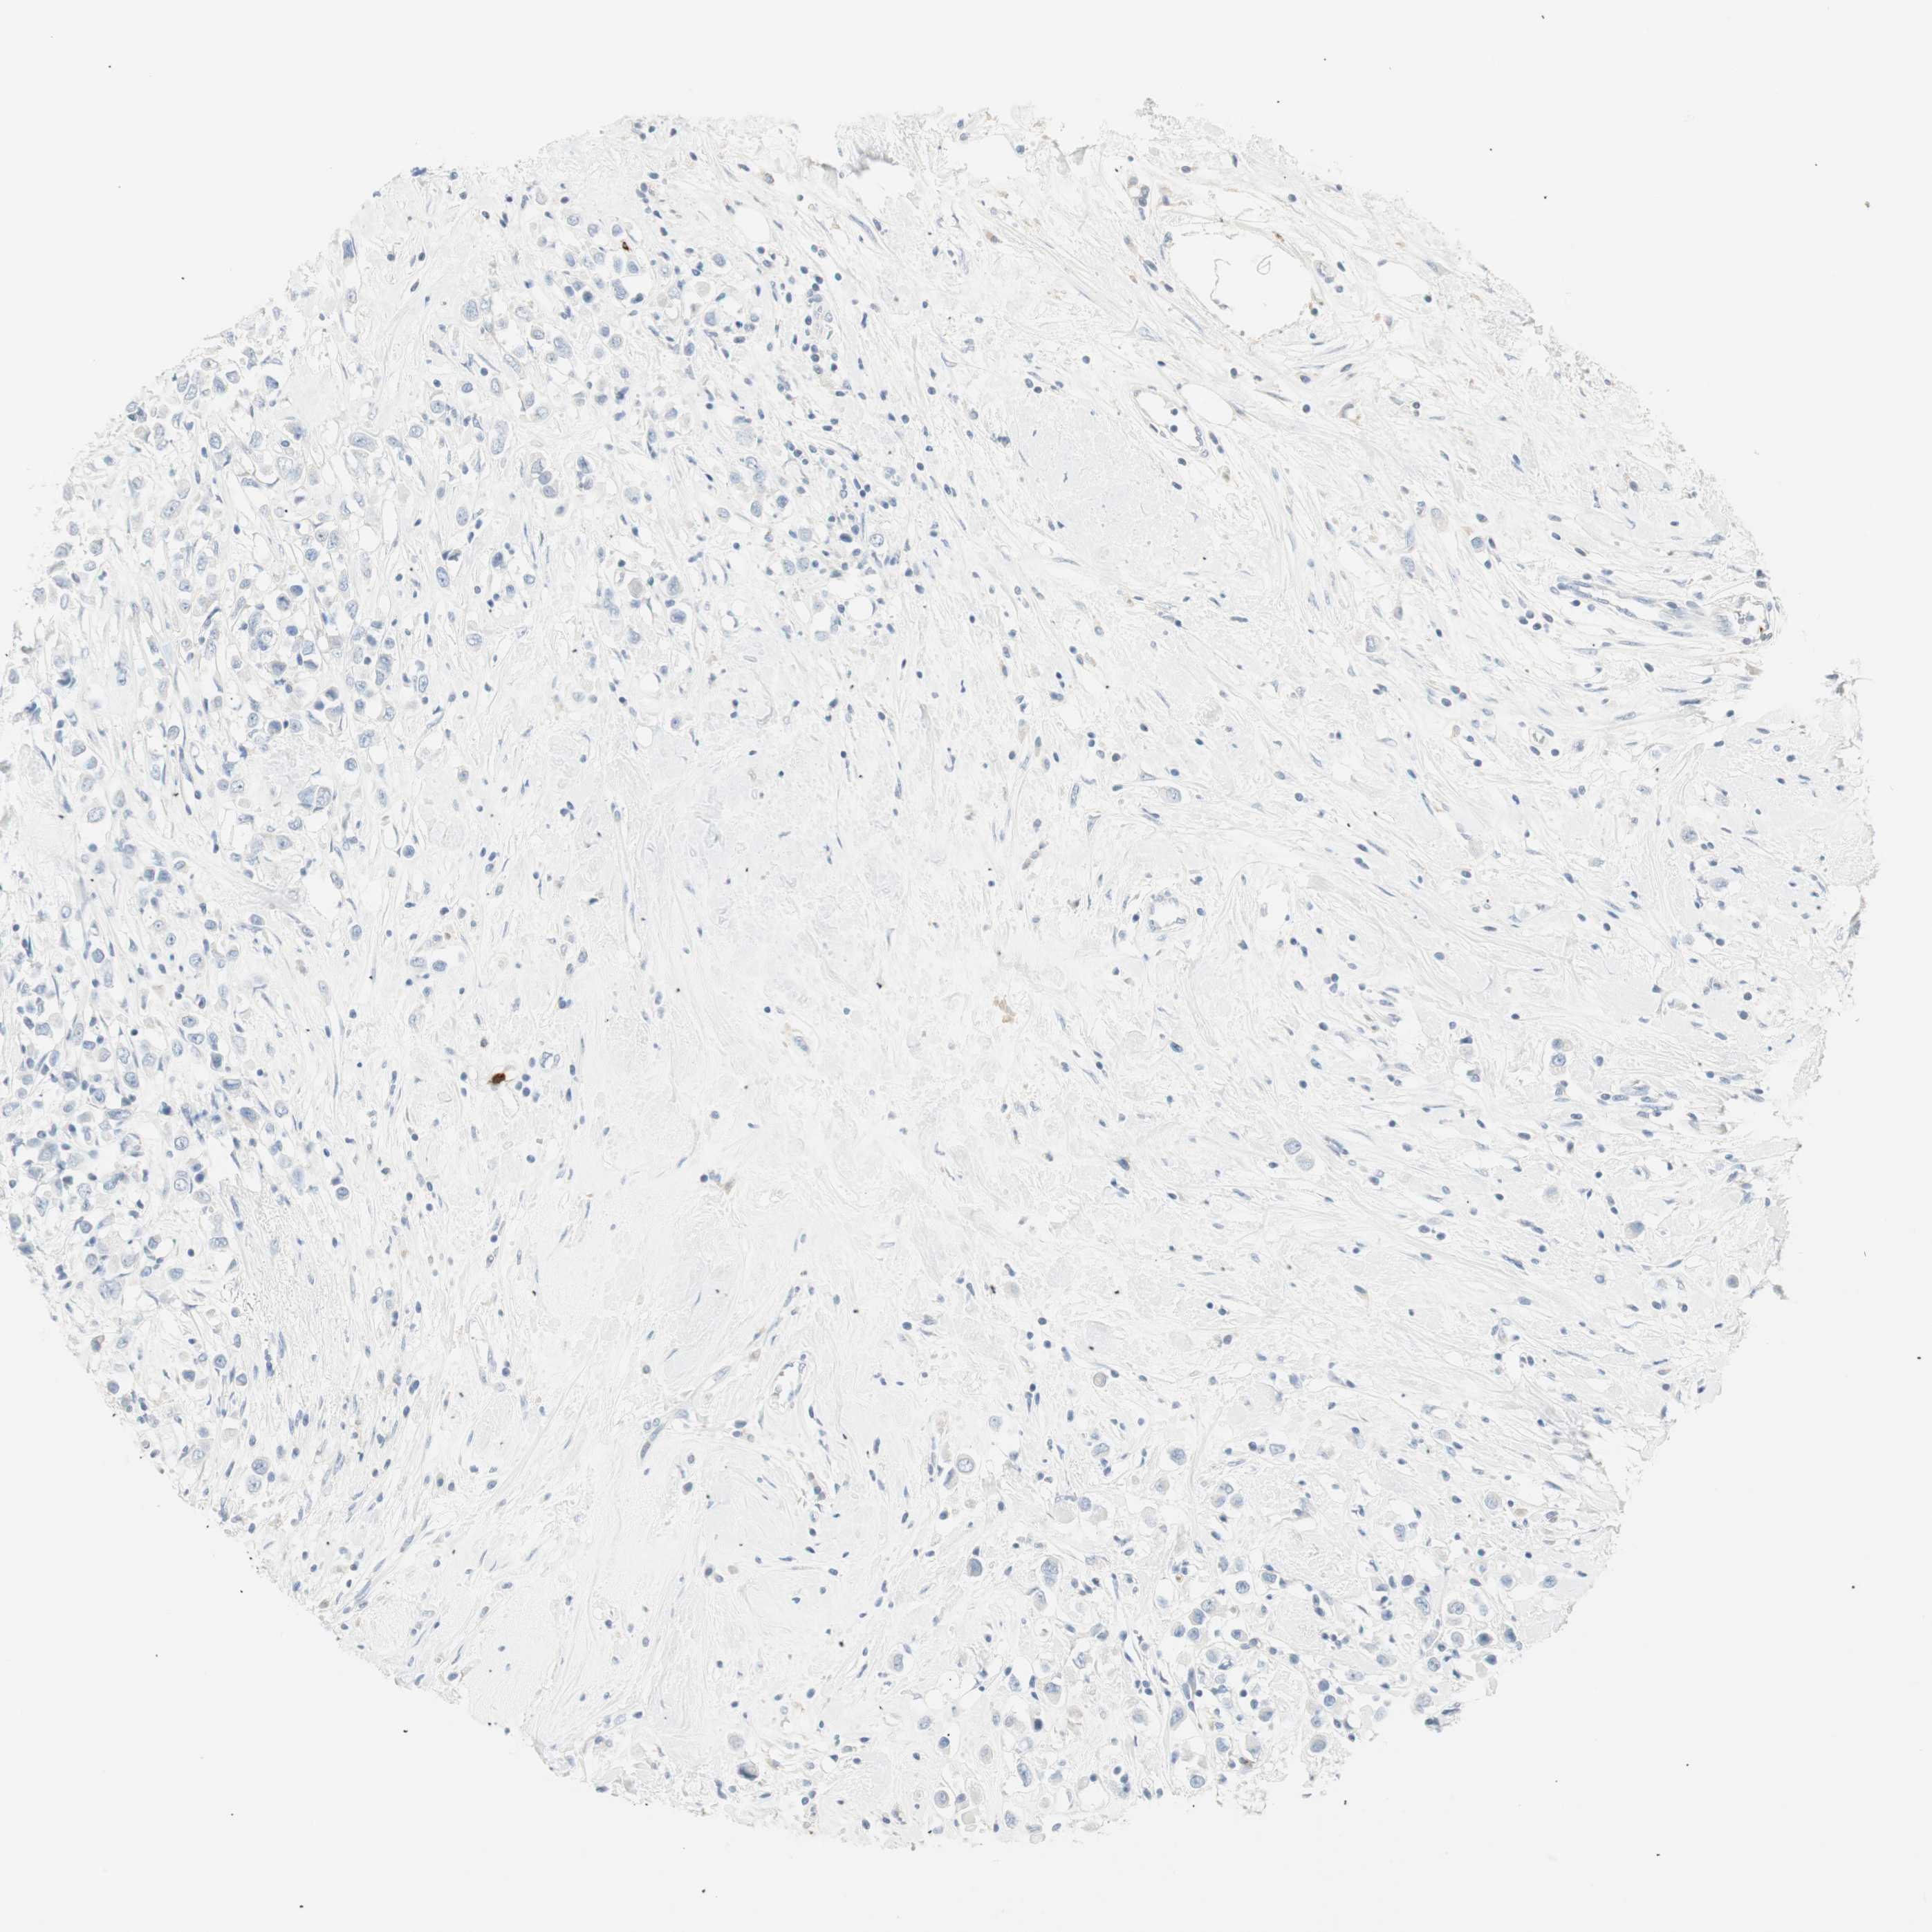

BRCA TCGA BRCA VALIDATION PROTEIN EXPRESSION

ANTIBODIES

AND

VALIDATION